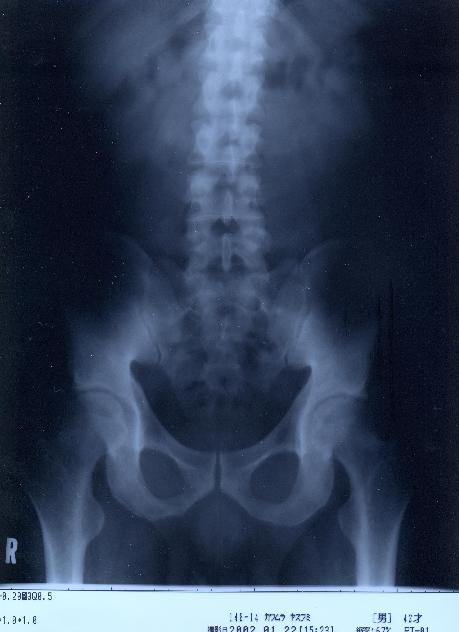

@@Ž„‚Μ”wœ‚Μ‚wόŽΚ^‚Ε‚·@@˜‚ͺ’Ι‚­‚Δ’Ι‚­‚āII@2002/1/22ŽB‰e

‚VD”wœ@@Šg‘ε